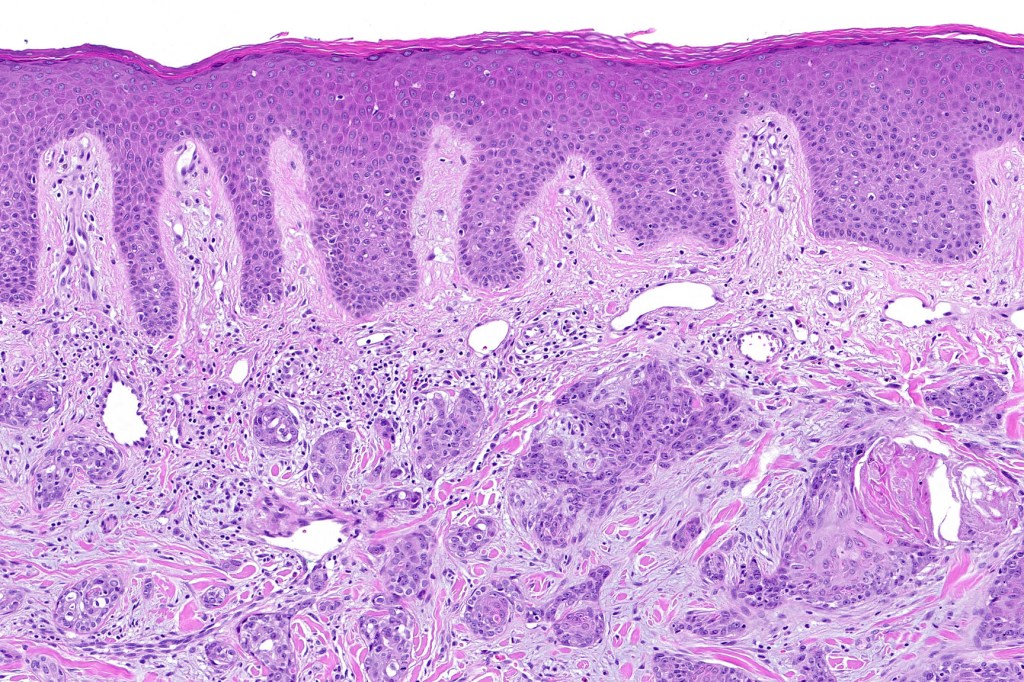

•Superficial SCC

•Adenocarcinoma in deeper reaches

•Deep part may show both ducts and glands